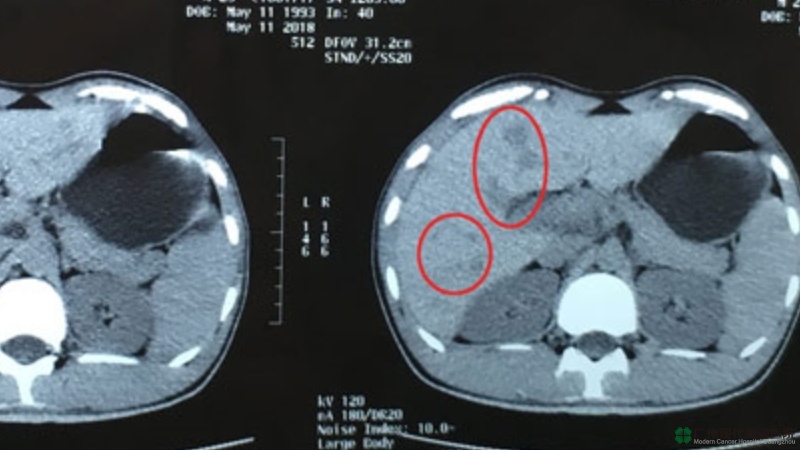

“Lúc tôi mới qua bệnh viện, bụng tôi đau lắm, người cũng rất mệt, tinh thần không tốt, hóa trị tại Việt Nam khiến tôi yếu vô cùng. Sau khi tôi làm những kiểm tra, bác sĩ phụ trách của tôi cô Hồ Doanh nói tôi bị ung thư túi mật đã di căn sang gan, trong gan có hai khối u lớn với kích thước 1.7cm*1.9cm và 1.1cm*1.3cm, và nhiều đốm nhỏ, và bác sĩ Hồ an ủi tôi phải yên tâm điều trị, bệnh tình có thể không chế.” anh Thụy nhớ lại tình hình ngày đâu tiên nhập viện và chia sẻ. Theo bác sĩ Hồ, bệnh tình của anh Thụy dù đã phát triển tới giai đoạn IV, nhưng khối u chỉ di căn tới gan, vẫn có thể khống chế được, sau khi đội ngũ MDT của bệnh viện thảo luận, họ đã đưa phác đồ điều trị cho anh Thụy là liệu pháp xâm lấn tối thiểu gồm có liệu pháp can thiệp + liệu pháp dao lạnh.

Đầu tháng 7 năm 2018, anh Thụy nhập viện tái khám và điều trị tiếp theo lời dặn của bác sĩ. Đây là lần thứ 3 anh Thụy nhập viện, lần này anh như người khỏe mạnh bình thường, anh đã không còn vẻ ốm yếu, cũng tăng 2 cân trong thời gian nghỉ dưỡng tại nhà, anh đã hồi phục lại sức lực của một thanh niên. Điều khiến anh phấn khởi nhất là kết quả kiểm tra CT cho thấy, hai khối u lớn 1.7cm*1.9cm và 1.1cm*1.3cm ở gan đã teo nhỏ khoảng 45%. Để củng cổ hiệu quả, lần này nhập viện, bác sĩ đã điều trị thêm một lần can thiệp nút mạch cho anh.

(Khối u trước khi điều trị dao lạnh vào tháng 5)

(Khối u teo nhỏ sau khi điều trị dao lạnh vào tháng 7)